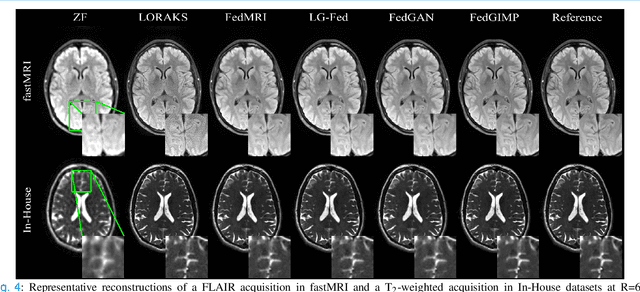

Abstract:Multi-institutional efforts can facilitate training of deep MRI reconstruction models, albeit privacy risks arise during cross-site sharing of imaging data. Federated learning (FL) has recently been introduced to address privacy concerns by enabling distributed training without transfer of imaging data. Existing FL methods for MRI reconstruction employ conditional models to map from undersampled to fully-sampled acquisitions via explicit knowledge of the imaging operator. Since conditional models generalize poorly across different acceleration rates or sampling densities, imaging operators must be fixed between training and testing, and they are typically matched across sites. To improve generalization and flexibility in multi-institutional collaborations, here we introduce a novel method for MRI reconstruction based on Federated learning of Generative IMage Priors (FedGIMP). FedGIMP leverages a two-stage approach: cross-site learning of a generative MRI prior, and subject-specific injection of the imaging operator. The global MRI prior is learned via an unconditional adversarial model that synthesizes high-quality MR images based on latent variables. Specificity in the prior is preserved via a mapper subnetwork that produces site-specific latents. During inference, the prior is combined with subject-specific imaging operators to enable reconstruction, and further adapted to individual test samples by minimizing data-consistency loss. Comprehensive experiments on multi-institutional datasets clearly demonstrate enhanced generalization performance of FedGIMP against site-specific and federated methods based on conditional models, as well as traditional reconstruction methods.